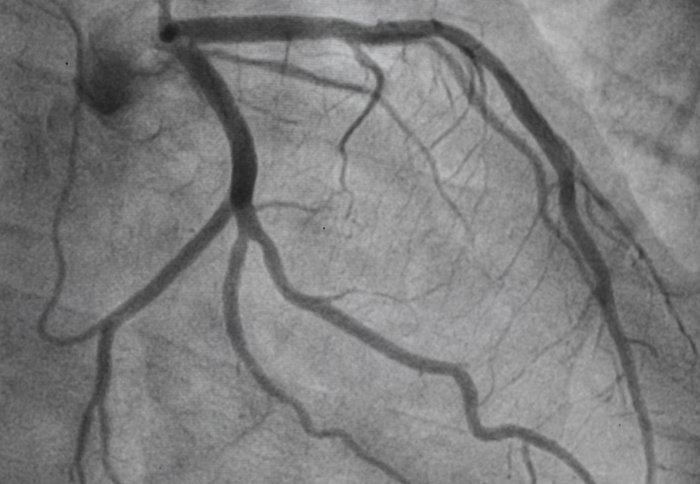

Coronary artery

Using stents to widen coronary arteries provides relief from symptoms